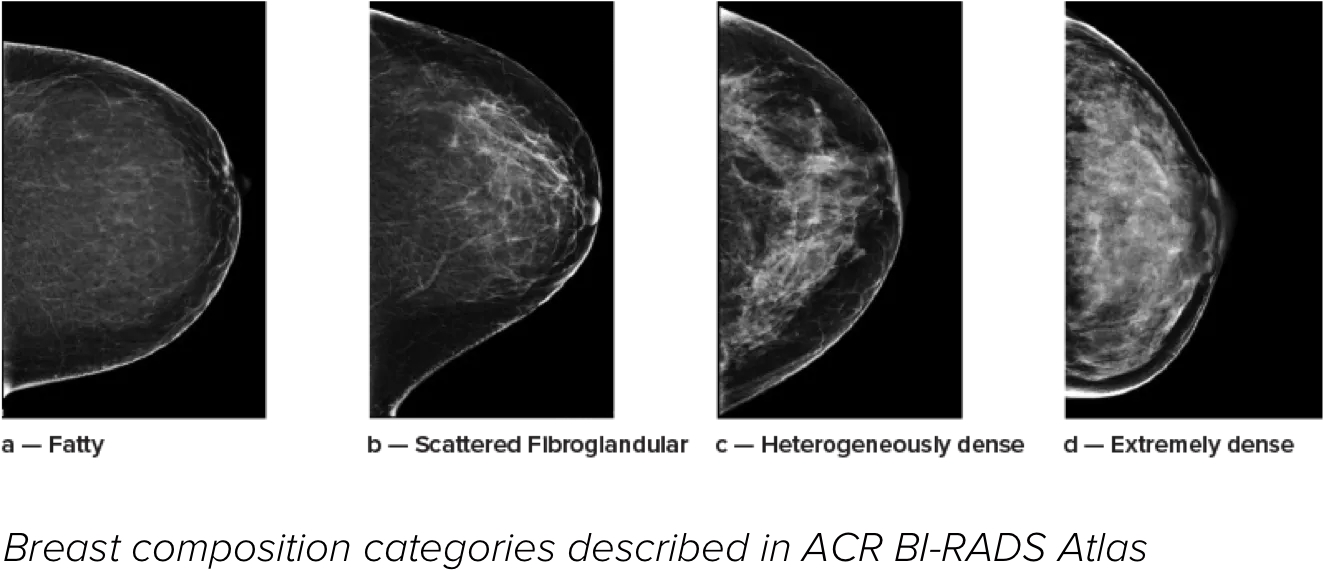

Det är känt att en hög brösttäthet ökar en kvinnas risk för bröstcancer.1 Behovet av noggrann och opartisk analys är därför kritiskt. Med hjälp av maskininlärning analyserar Quantra Technology-programvaran både 2D™- och tomosyntesbilder för fördelning och textur av parenkymal vävnad. Den kategoriserar bröst i fyra bröstkategorier utifrån sammansättning enligt riktlinje från American College of Radiology (ACR) BI-RADS Atlas 5th Edition.2

* Poängbedömningar baseras på ACR BI-RADS-kategorier enligt de reviderade riktlinjerna från American College of Radiation (ACR) BI-RADS Atlas 5th Edition. Detta motsvarar mönster och textur jämfört med volym vid bedömning av täthet.

8. Kategorier för bröstsammansättning enligt beskrivningen i ACR BI-RADS Atlas.